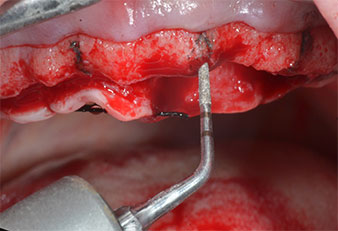

Due to the relatively hard bone (D2) in this area, the 10 mm long implant sites at positions 11 and 21 were finalized with a 4 mm diameter rotary drill, in combination with a W&H WS-75 L surgical contra-angle handpiece, the W&H Implantmed implant motor and the optional W&H Osstell ISQ module. In contrast, due to the soft bone the posterior sites were prepared to a final 3 mm diameter using the Piezomed I3P instrument. The implants were finally placed transgingivally to osseointegrate for three months (Figs. 6-10). The existing denture was retained on four provisional implants (Fig. 8).